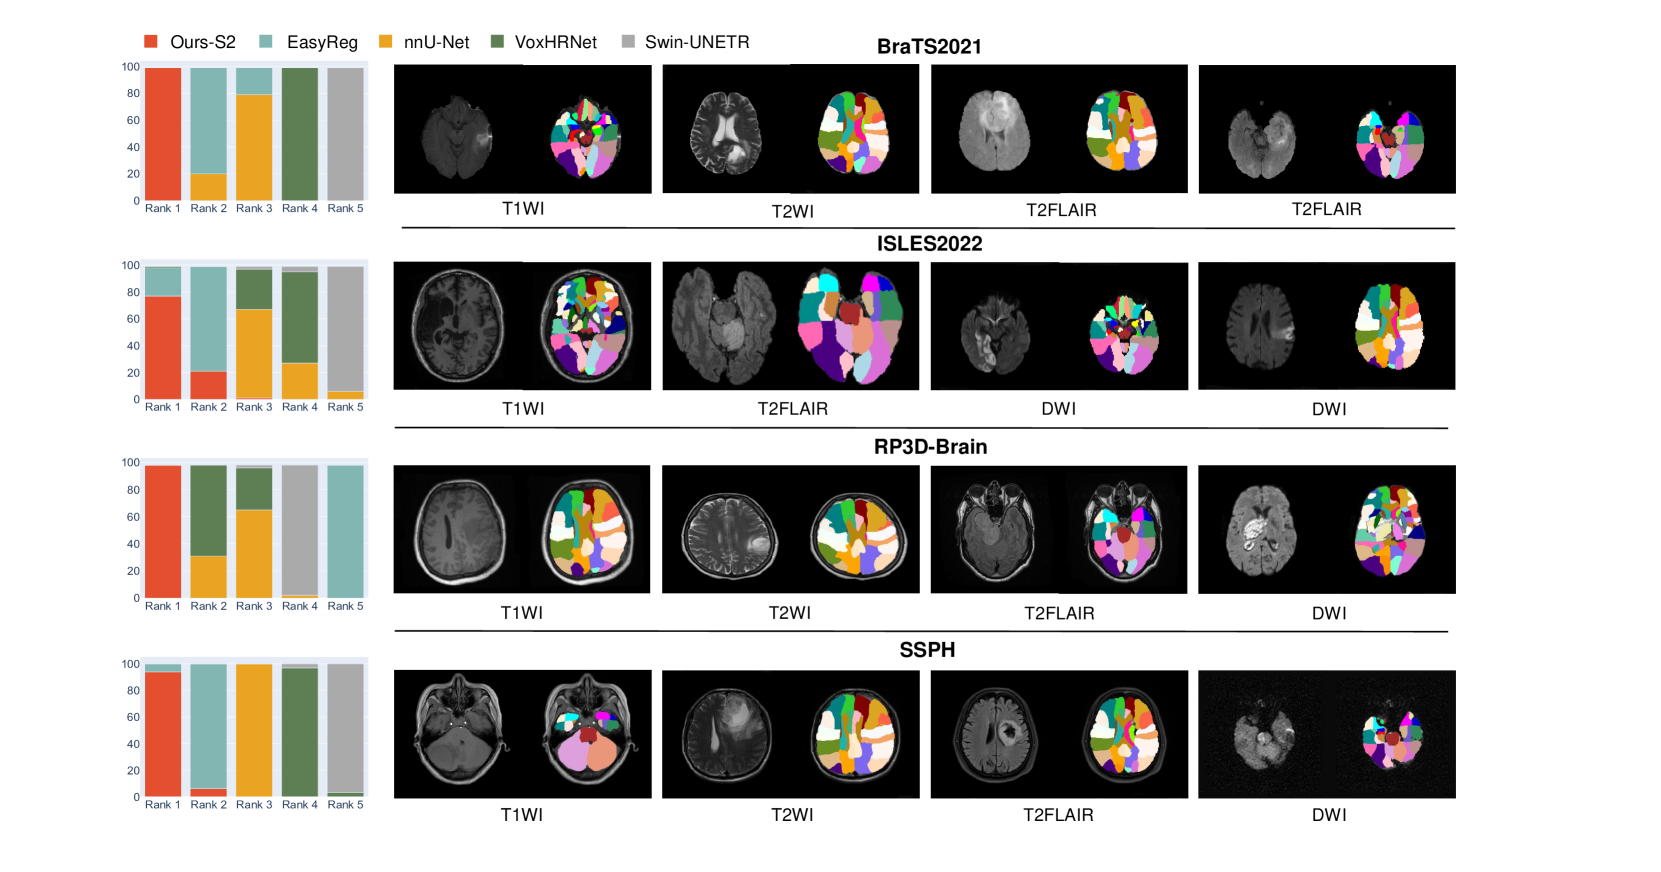

Refer to caption

Figure 2: Comparison of our second-stage segmentation module (Ours-S2) with SOTA segmentation backbones and brain registration models on brain structure segmentation for multi-modal brain MRIs with real anomalies. We evaluate these models on four distinct datasets, BraTS2021, ISLES2022, RP3D-Brain, and SSPH. Due to the absence of ground truth brain structure segmentation on those datasets, we present the results based on human rankings on the left, where lower rankings indicate better outcomes. Note the baseline nnU-Net is not the same structure as our segmentation module, since we modify the original nnU-Net to fit our problem scenario.

To further verify the brain structure segmentation ability of Ours-S2 on multi-modal brain MRIs with real anomalies, we invite two radiologists to rank the predictions from our model (Ours-S2) and baseline models on scans with various anomalies, derived from ISLES2022, BraTS2021, RP3D-Brain, and SSPH. As shown in Fig. 2, predictions from Ours-S2 are mostly ranked as the top, and the structure segmentation results of Ours-S 2 are displayed on the right. In general, AutoRG-Brain currently demonstrates the best performance on brain structure segmentation for multi-modal lesion-induced brain MRIs across different datasets.